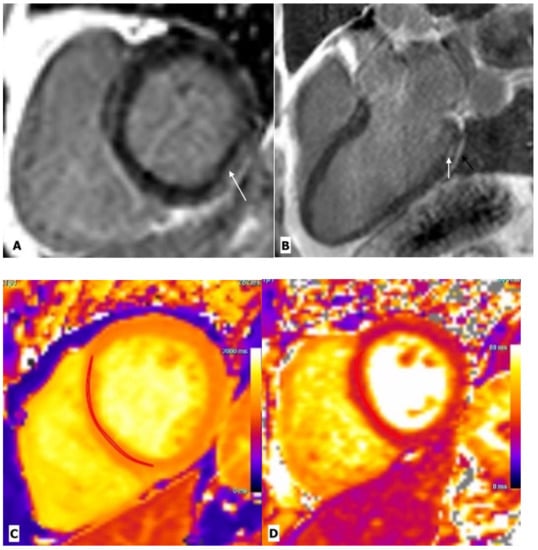

2.1. Myocarditis

| Myocarditis | Luetkens, J.A. et al. | Prospective cohort study | 28 patients and 22 control subjects | CMR | Compared with healthy controls, HIV-infected patients showed lower ejection fraction, lower global strain values, elevated native T1 and T2 values, and myocardial fibrosis, predominantly at the subepicardial of the midventricular and basal inferolateral wall. |

| Ntusi, N. et al. | Cross sectional observational study | 103 patients and 92 control subjects | CMR | Compared with controls, HIV-infected patients had lower LVEF, higher myocardial mass, lower peak diastolic strain rate, and higher native T1 values. Pericardial effusions and myocardial fibrosis were 3 and 4 times more common, respectively, in subjects with HIV infection. | |

| Robbertse et al. | Prospective study | 73 patients and 22 healthy controls | CMR | Compared with controls, a significant decrease in native T1 and ECV was seen after 9 months of HAART in HIV patients, which was significantly associated with a decrease in C-reactive protein, a decrease in HIV viral load, and an improvement in CH4 count. | |

| De Leuw et al. | Prospective observational study | 156 patients | CMR | Patients with higher ECV values have a higher rate of cardiovascular outcomes. | |